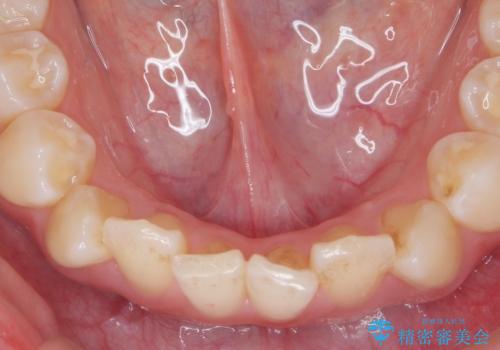

インビザラインライトで行う短期マウスピース矯正治療

- 前歯のガタつきを並べたいたいと、矯正治療を希望され来院されました。

とにかく短期間で前歯だけの治療を行いという希望が強く、全体矯正と前歯だけの部分矯正の仕上がりのイメージを確認したのち14枚のマウスピースで前歯のみの矯正治療を行っていくこととしました。